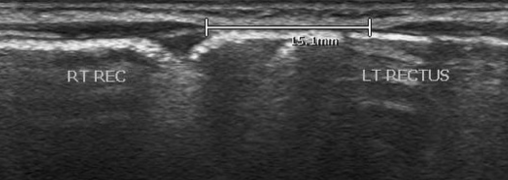

- >15-25mm pathologique environ

- Fait des hernies mais sans risque de strangulation (pas des vraies hernies)

- Decrire si diastasis supra-ombilical ou infra-ombilical